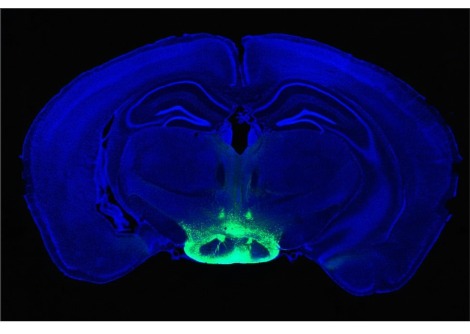

في عام 2023، حاول باحثون في جامعة بنسلفانيا استخدام كبد خنزير معدل وراثيًا كجهاز احتياطي، حيث تم توصيل العضو خارجيًا بشخص توفي مؤخرًا. وتمكن الفريق من تدوير دم الشخص من خلال كبد الخنزير، وهي خطوة نحو استخدام العضو للقيام مؤقتًا بمهام الكبد لدى مرضى فشل الكبد. وفي الحالة الجديدة، أدخل الجراحون الكبد إلى داخل الجسم. بدأ الفريق بخنزير باما مصغر، حُذفت منه بعض جينات الخنزير، وأُضيفت إليه جينات بشرية. تلعب هذه الجينات دورًا في رفض عملية الزرع؛ وكان الهدف من هذه التعديلات تقليل احتمالية فشل عملية الزرع.